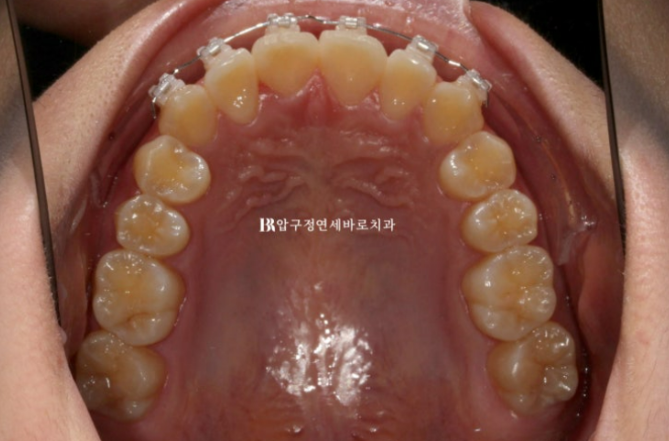

앞니 부분교정은 앞니 6개에만 장치를 붙여 진행합니다.

덧니는 거의 해결이 되었고 고무줄을 걸어 앞니 교합은 깊어지지 않도록 도모했습니다.

심한 덧니를 가지런하게 하기 위해서 치간삭제도 소량 들어갑니다.

그리고 한달 후 24년 6월 드디어 덧니 부분교정 앞니교정 단기교정 마무리 !

24.06